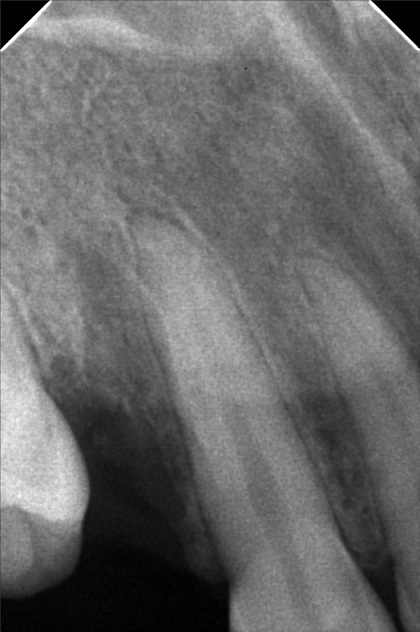

- 9/17/22- OP(LIGHT). RESTO #16 CLASSII MO, LINGUAL , Gingivectomy 9/24/22 - EXO #14, 1 GEL FOAM, SUTURE

- banalo_janelle.jpg